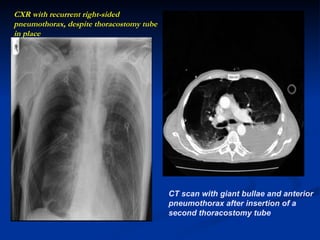

Twist in Tale..

CXR with recurrent right-sided pneumothorax, despite thoracostomy tube in place CT scan with giant bullae and anterior pneumothorax after insertion of a second thoracostomy tube

CXR with recurrentright-sided pneumothorax, despite thoracostomy tube in place CT scan with giant bullae and anterior pneumothorax after insertion of a second thoracostomy tube